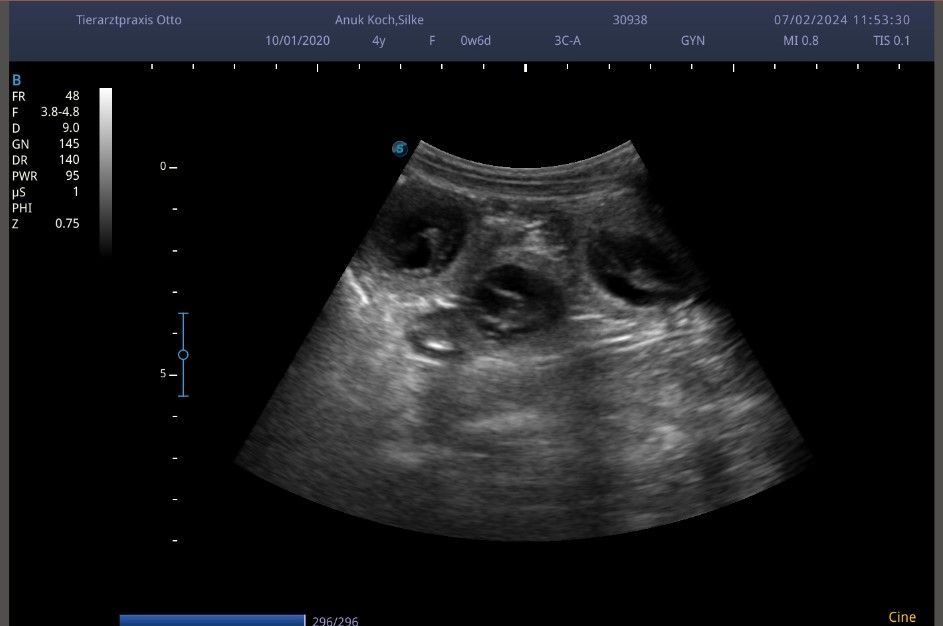

07.02.2024

Heute war es endlich soweit. Obwohl bereits alle Anzeichen dafür sprachen sind wir mit unserer Anouk zum Ultraschall gefahren. Wir freuen uns riesig denn unser Anouk ist trächtig, der Wurf wird voller Freude Anfang März erwartet.

Bei Interesse an einem Welpen aus dieses wundervollen und sehr interessanten Verbindung aus besten Linien können sie vorab gerne mit uns in Kontakt treten.

Es gibt wundervolle Neuigkeiten. Heute war unser Ultraschall Termin mit Phoebe. Insgeheim ahnte ich es ja schon da alle Anzeichen dafür sprachen. Aber jetzt ist es sicher.....Zu Silvester dürfen wir mit kleinen Silken Diamonds von Phoebe und Ryan rechnen .